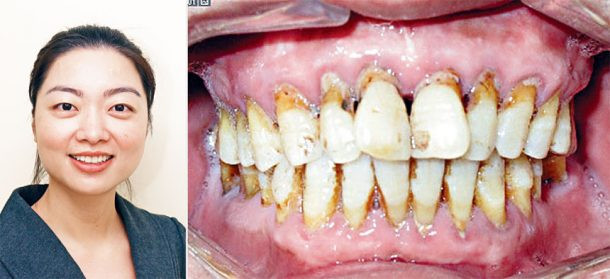

醫術精湛能提供全面牙齒照顧之容淑萍牙醫擅长醫治牙周病之容淑萍牙醫指出,牙周病是僑胞常見之牙患,如不及時治療會導致牙齦收縮牙齒脫落。

容醫生指出:牙周病是一般華人常見的牙疾,一般35歲以上的成年人都會患有輕度、中度或嚴重牙周炎,假如發現得早,加上適當的治療,大部分都可以醫治。

牙周病是一種漸進性疾病,是由於細菌侵蝕牙齦和牙齒分離,導致牙齦和支持牙齒的骨骼發炎或受感染,若不及早治療,牙周炎會令牙肉收縮,破壞牙肉及牙骨組織,從而使牙肉發生紅腫,含膿,鬆弛和容易流血、情況會越來越壞,到了晚期,發炎的牙齦會和牙齒分離,支持的骨骼也被破壞,牙齒鬆動,最終要拔掉。